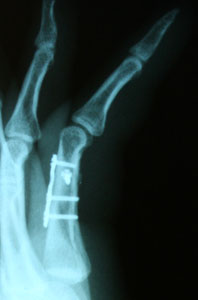

Остеосинтез пальца руки

Остеосинтез пальца руки 105 фото